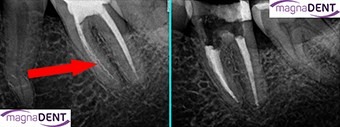

Wykonujemy wysoce specjalistyczne zabiegi leczenia kanałowego pod mikroskopami operacyjnymi, przy zastosowaniu najnowszych zdobyczy medycyny mikoinwazyjnej i odtwórczej, rutynowo lecząc także powikłania. Usuwamy złamane instrumenty endodontyczne pozostawione w kanałach korzeniowych, zamykamy perforacje w ścianach kanałów korzeniowych, regenerujemy uszkodzoną kość w okolicy wierzchołków korzeni, stymulujemy zatrzymany rozwój korzeni stałych zębów martwych u dzieci i młodzieży, odtwarzamy utracone tkanki twarde w okolicy szczytów korzeni zębów na skutek procesów zapalnych, leczymy zęby z nietypową anatomią (bardzo wąskie oraz zakrzywione kanały korzeniowe, dodatkowe kanały, niestandardowe lokacje kanałów), wykonujemy leczenia kanałowe w przypadku wad rozwojowych/genetycznych zębów (zęby wgłobione, zęby taurodontyczne, hypoplazja zębiny etc.).

Specjalizujemy się w ratowaniu zębów, które standardowo zostałyby zakwalifikowane do usunięcia. Poza mikroskopami operacyjnymi stosujemy do opracowania kanałów korzeniowych narzędzia rotacyjne i recyprokalne z stali marstenicznej sterowane komputerowo, wysoce efektywne protokoły dezynfekcji i płukania systemu kanałowego zęba za pomocą specjalnych środków chemicznych aktywowanych ultradźwiękami oraz specjalne systemy do wypełniania kanałów korzeniowych termicznie uplastycznianą gutaperką z uszczelniaczami na bazie bioceramiki.

Przed właściwym zabiegiem ZAWSZE jest wykonywana krótka (15-20 min) wizyta diagnostyczna, na której wykonywane jest aktualne zdjęcie RVG w wysokiej rozdzielczości, przygotowywany jest pisemny plan leczenia wraz z kosztorysem oraz przeprowadzana jest kwalifikacja danego zęba do leczenia kanałowego. Pacjent zawsze otrzymuje pełną informacje o stanie zęba, planowanym zabiegu, potencjalnym ryzyku, szansach powodzenia, postępowaniach alternatywnych oraz konsekwencjach odstąpienia od leczenia.